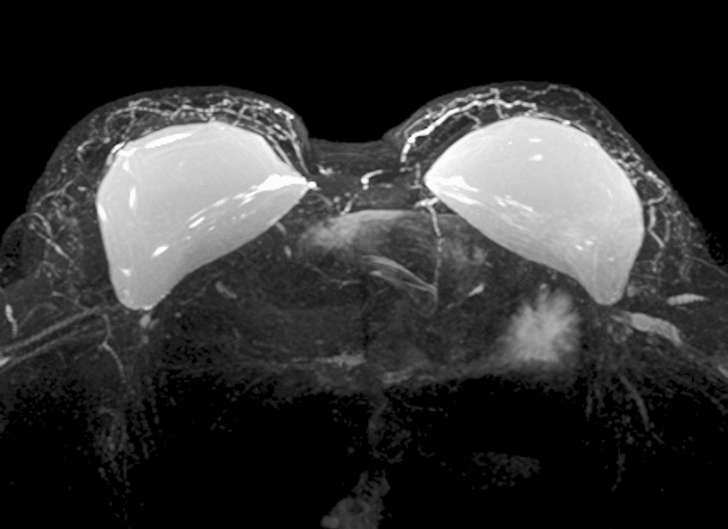

6. Силіконові груди в апараті МРТ

20 знімків, які раніше бачили тільки рентгенологи. А тепер можете і ви